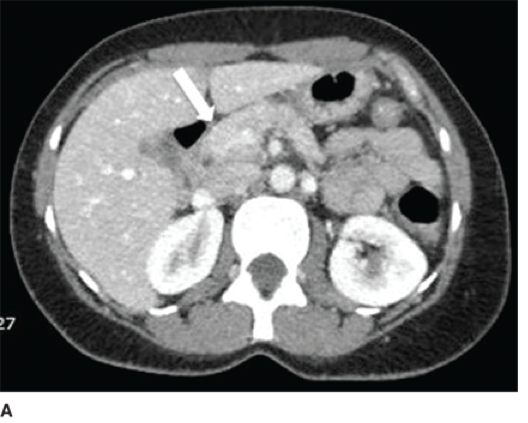

mucinous cystic neoplasm

A

o Women

o Body or tail pancreas

o Painless, slow growing mass

o 1/3 assoc. w/ invasive carcinoma

o The cysts are lined by columnar mucinous epithelium, and a dense ovarian-type stroma

o Not involving the major pancreatic duct